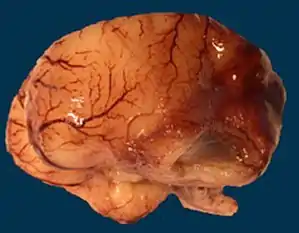

| Microlissencephaly in a 27 WG (week of gestation) foetus with TUBB2B mutation. Macroscopical view of the left hemisphere showing agyria, absent sylvian fissure and absent olfactory bulb. | |

Microlissencepahly is considered a tubulinopathy (tubulin gene defect)[30] i.e. is caused by mutation in tubulin genes, mainly TUBA1A[31] and less commonly TUBB2B, TUBB3, TUBA3E and TUBG1.[32] Central pachygyria, polymicrogyria are more commonly seen in patients with defects in TUBB2B, TUBB3, and TUBB5.[33] This implys the critical role of microtubule cytoskeleton in the pathophysiology of microlissencephaly as well as other neuronal migration disorders.[20]